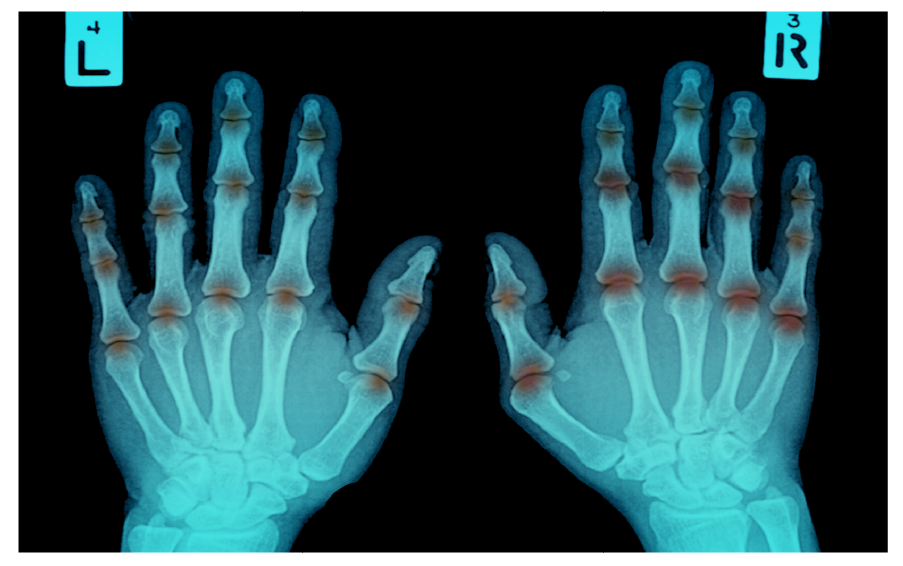

| Stages | Radiological charges |

|---|---|

| I | Only soft tissue swelling |

| II | Periarticular osteoporosis, Increased joint space (Effusion) |

| III | Loss of articular cartilage (Decreased joint space) |

| IV | Erosion |

| V | Subluxation and ankylosis |